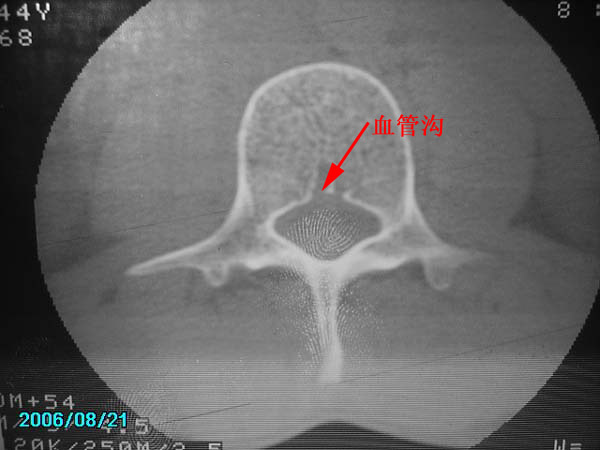

除有第3-5腰椎椎体后缘中央血管沟显示外,诸椎间盘比较正常。我也象13081830109战友那样看见了指纹,呵呵。

以下是引用守望可可西里在2006-11-13 22:44:00的发言:[br][br]  除有第3-5腰椎椎体后缘中央血管沟显示外,诸椎间盘比较正常。我也象13081830109战友那样看见了指纹,呵呵。